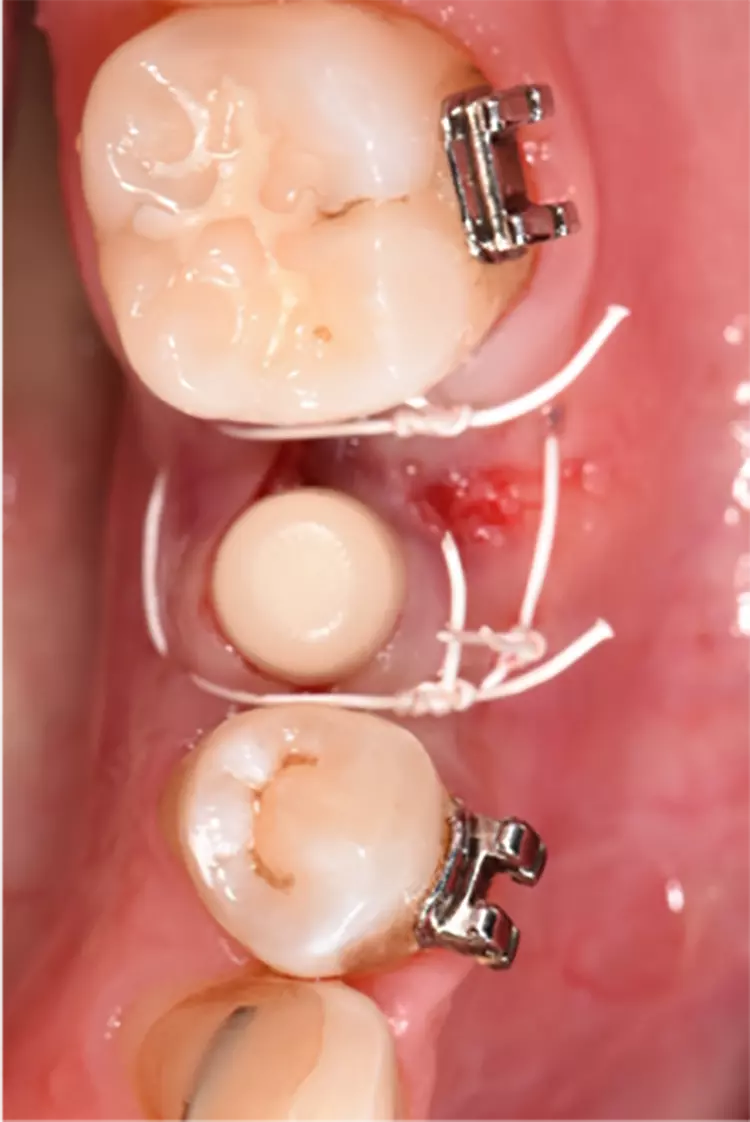

Die Implantate wurden im üblichen chirurgischen Vorgehen inseriert und sofort mit einem Provisorium aus Polymethylmethacrylat (CAD-Temp, VITA) versorgt, wobei die Provisorien außer Okklusion geschliffen wurden und darauf geachtet wurde, dass approximal nur sehr schwache Kontakte bestanden (Abb. 3a bis e). Die definitive prothetische Versorgung erfolgte im Unterkiefer nach frühestens 2 Monaten, im Oberkiefer nach frühestens 4 Monaten. Die Restaurationen wurden aus verblendetem Zirkonoxid hergestellt (VITA YZ HT / VITA VM 9, VITA).

Bei Knochendefekten ist eine Augmentation erforderlich. In der klinischen Studie „FR/ZH“ wurden in 11 Fällen kleinere simultane Augmentationen durchgeführt (vergl. Abb. 3). Die Augmentationen dürfen aufgrund der ermittelten Sondiertiefen und Röntgenbefunde als erfolgreich angesehen werden.